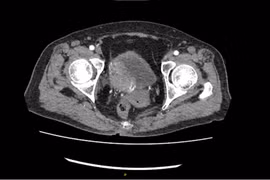

Các bác sĩ thận tiết niệu gọi trường hợp có 2 bàng quang này là “tôn hành giả - giả hành tôn”: bàng quang “thật” và bàng quang giả - thực chất là túi thừa bàng quang.

Khi mắc túi thừa bàng quang, người bệnh sẽ cảm thấy đau, nhiễm trùng tiết niệu nhiều lần và rối loạn tiểu tiện do nước tiểu không chảy hết ra ngoài mà đọng lại… Bệnh không chỉ gây rất khó chịu mà còn biến chứng nguy hiểm.